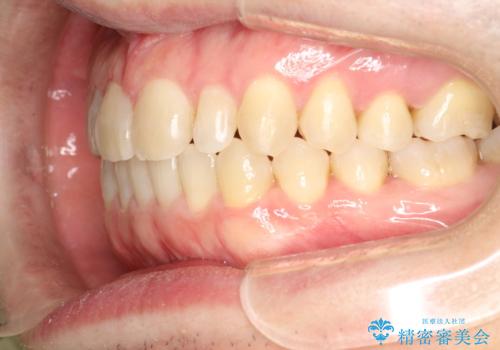

前歯の真ん中の隙間を閉じたい インビザラインによる目立たない矯正

- 上顎の正中の隙間が気になるとのことで来院されました。

下の歯と歯の間をわずかに削り、スペースを作り、正中の隙間を閉じる計画としました。

装置はインビザラインにて行いました。

インビザラインで目立たずに矯正治療を行うことができました。

使用時間を守っていただけたので、比較的スムーズに矯正を終了することができました。